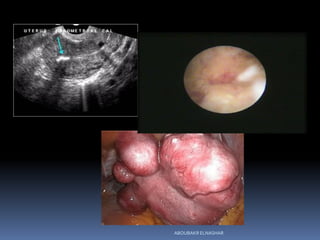

I. Infertility investigation:

 No specific findings: unexplained infertility

 Age related factors:

Endometriosis

Fibroids

Polyps

:Assessment of uterus